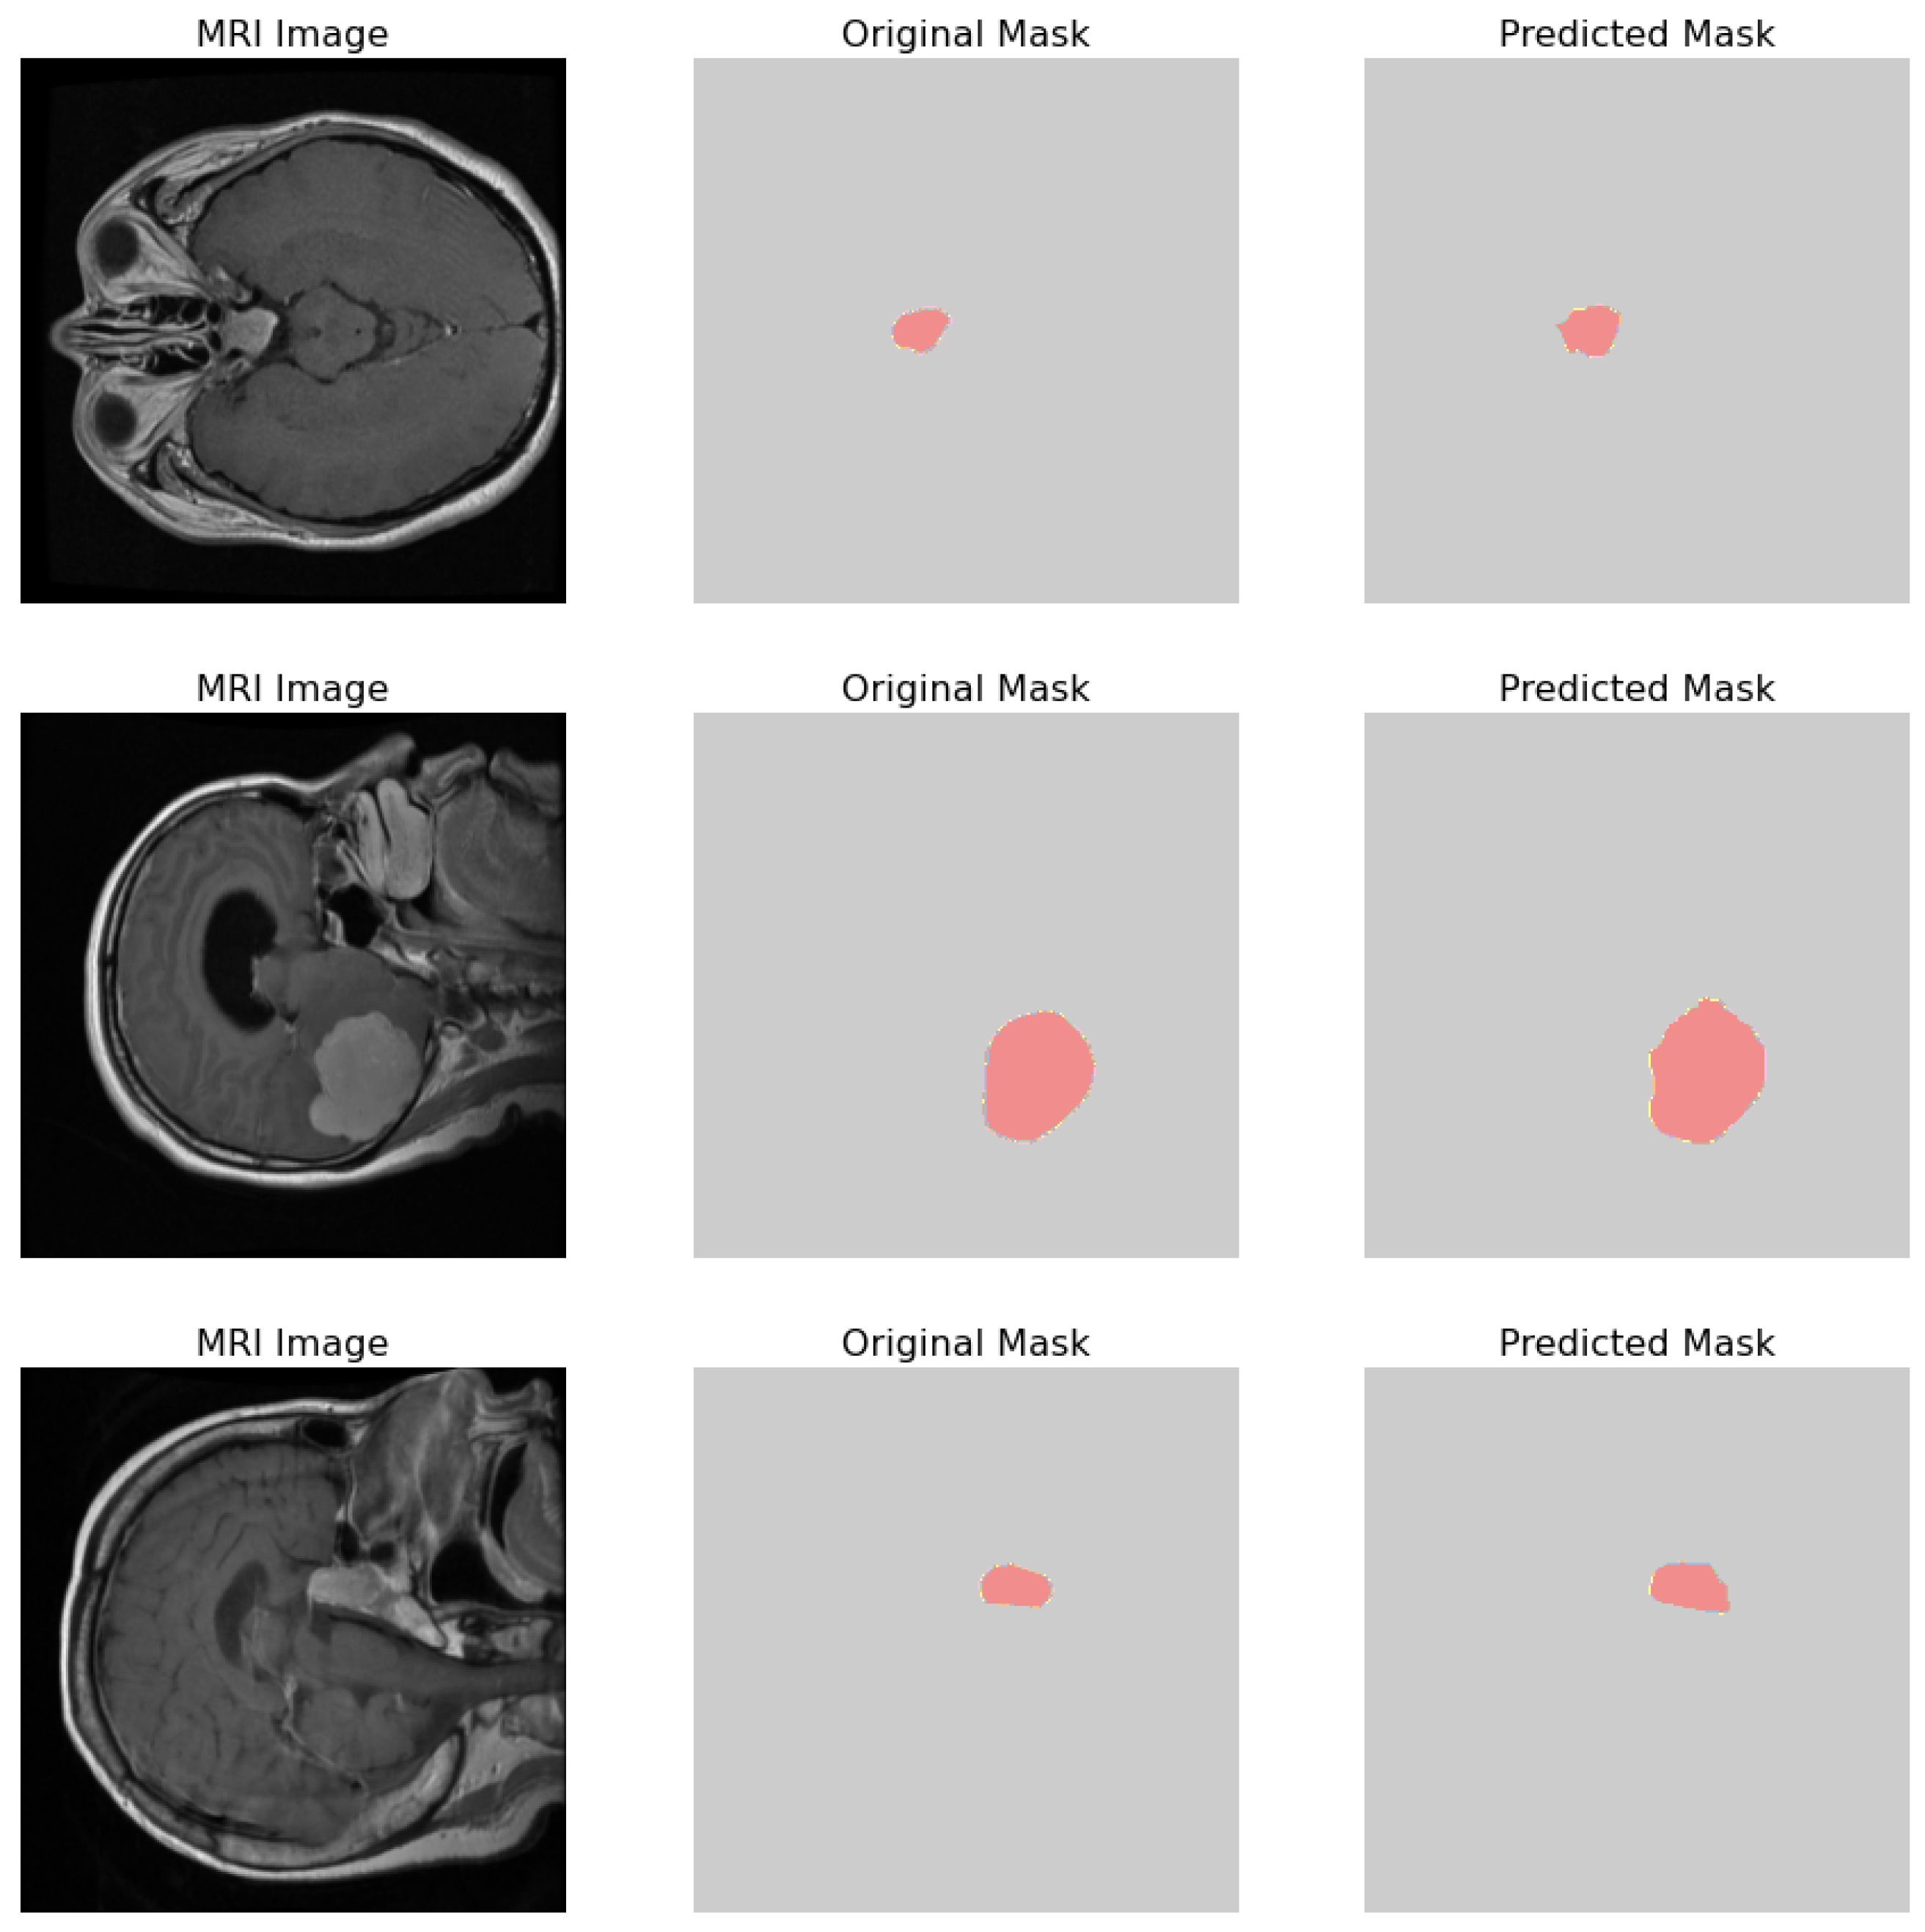

3.1. Proposed Model Generalization

3.3. Second Dataset (Classification and Segmentation Task)